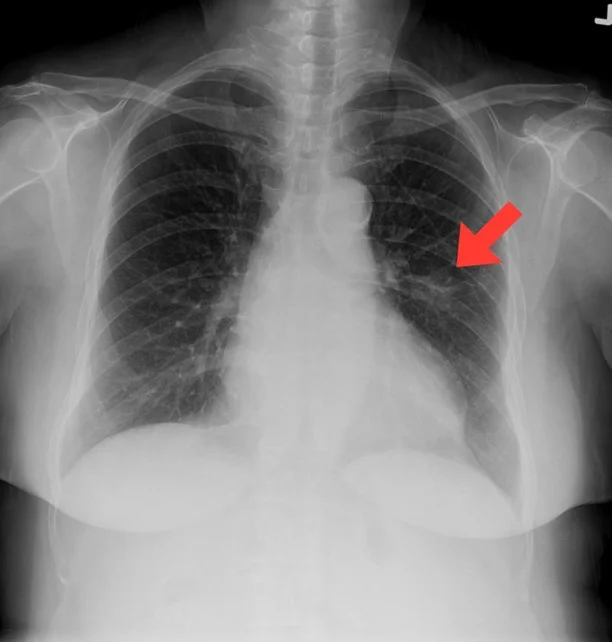

ลักษณะความผิดปกติที่พบจาก X-ray

ในบริเวณพื้นที่ปอดจากภาพถ่าย X-ray ซึ่งจะเห็นเป็นสีดำๆ รูปร่างของปอดในช่องอก ทั้ง 2 ข้าง และจะมีเส้นสีขาวๆจางๆ กระจายจากศูนย์กลางแผ่ไปจนเกือบสุดรอบนอกของปอดทุกๆด้าน ซึ่งจะแสดงถึงเส้นเลือดในปอด การตรวจพบความผิดปกติ มักจะเจอเป็นก้อน ปื้นๆสีขาวๆ เด่นชัดขึ้นมาจากพื้นที่ของปอด(พื้นสีดำ) โดยขนาดที่จะเห็นชัดเจนได้คือประมาณ เกือบ 1 เซนติเมตร เป็นต้นไป ซึ่งขึ้นอยู่กับความหนาแน่นของก้อนด้วย ถ้าก้อนหนาแน่นมาก จะพบเป็นสีขาวชัดๆ (อาจเห็นตั้งแต่ขนาดเล็กๆมากๆตั้งแต่ 2-3 มิลลิเมตรเลย) แต่ถ้าก้อนหน้าแน่นน้อยๆ จะมองเห็นได้ยาก บางครั้งก้อนใหญ่กว่า 1 เซนติเมตรแต่หนาแน่นน้อย จะเป็นปื้นที่จางๆมาก จนอาจไม่สามารถตรวจพบได้ในครั้งแรกได้เช่นกัน นอกจากนี้เนื่องจากภาพ X-ray เป็นภาพ 2 มิติ จึงอาจมีบางตำแหน่งที่ภาพซ้อนทับกันจนทำให้ตรวจไม่พบก้อนได้ เช่นบริเวณ หลังเงาหัวใจ บริเวณช่วงล่างของปอดที่ถูกกระบังลมและอวัยวะในช่องท้องมาบดบังจนมองไม่เห็นเงาผิดปกติใน

ปอด (ด้วยเหตุนี้ Low Dose CT จึงตรวจได้แม่นยำกว่า เพราะแสดงภาพได้ทั้ง 3 มิติ)